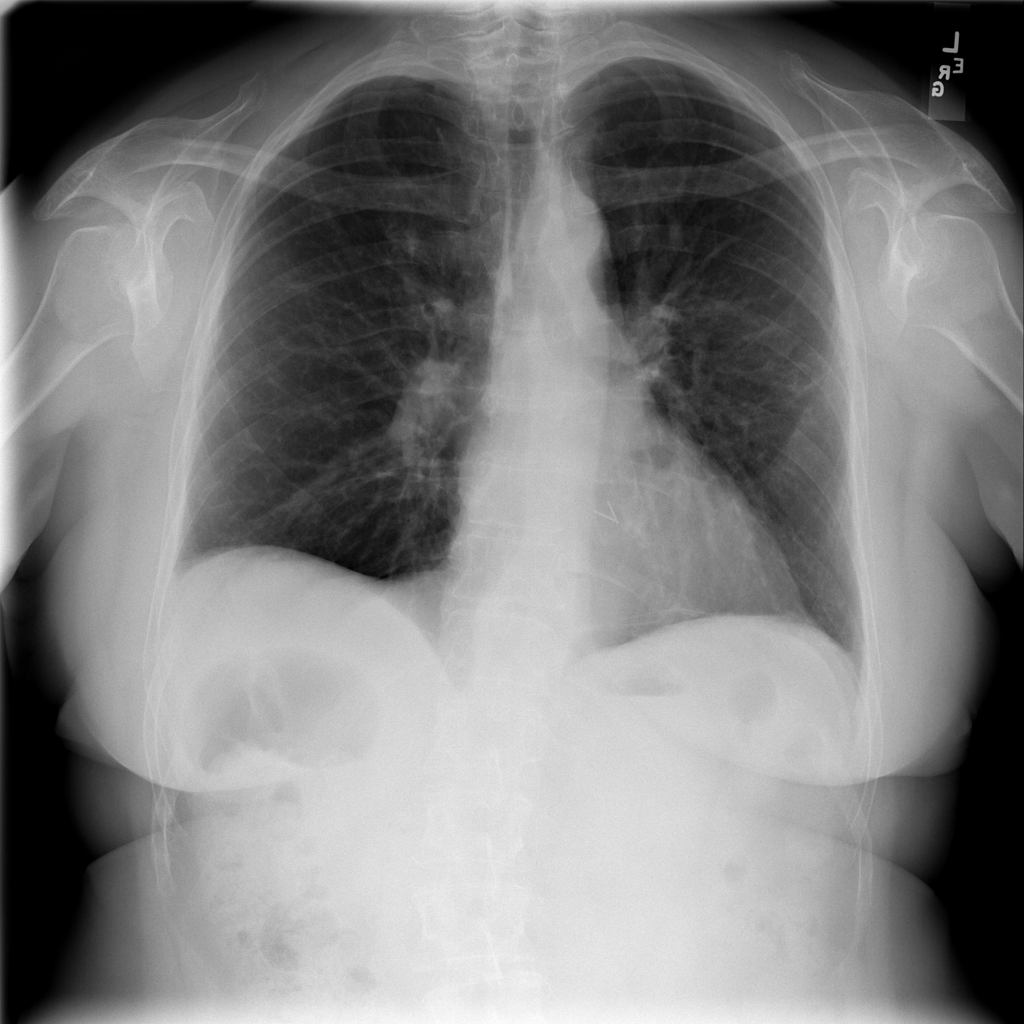

PAT-C77C · IMG-003Fibrosis

PAT-C77C · IMG-003

PA